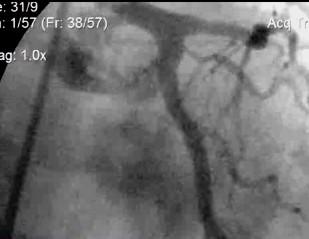

«Через кожные проколы, входя инструментами специальными в артерии или вены под контролем ангиографа – специальная рентгенустановка, в разных плоскостях работающая над больным, позволяющая с помощью контрастных веществ доходить до пораженного органа. Основной пласт проблем, которые решает рентгенхирургия – это либо включение в кровоток пораженного участка, либо выключение из кровотока патологического органа».

Первые – это в основном сосуды, пораженные атеросклерозом. Специальными инструментами расширяются суженные участки и ставят туда стенты, тем самым восстанавливая кровоснабжение пораженного органа.

Для того чтобы найти тромб или сужение, в сосуд вводят специальную жидкость. На этих кадрах хорошо видно, где жидкость проходит свободно, а где нет. Именно над этими «слабыми» места и работают хирурги. Что раньше являлось противопоказанием для хирургического вмешательства».